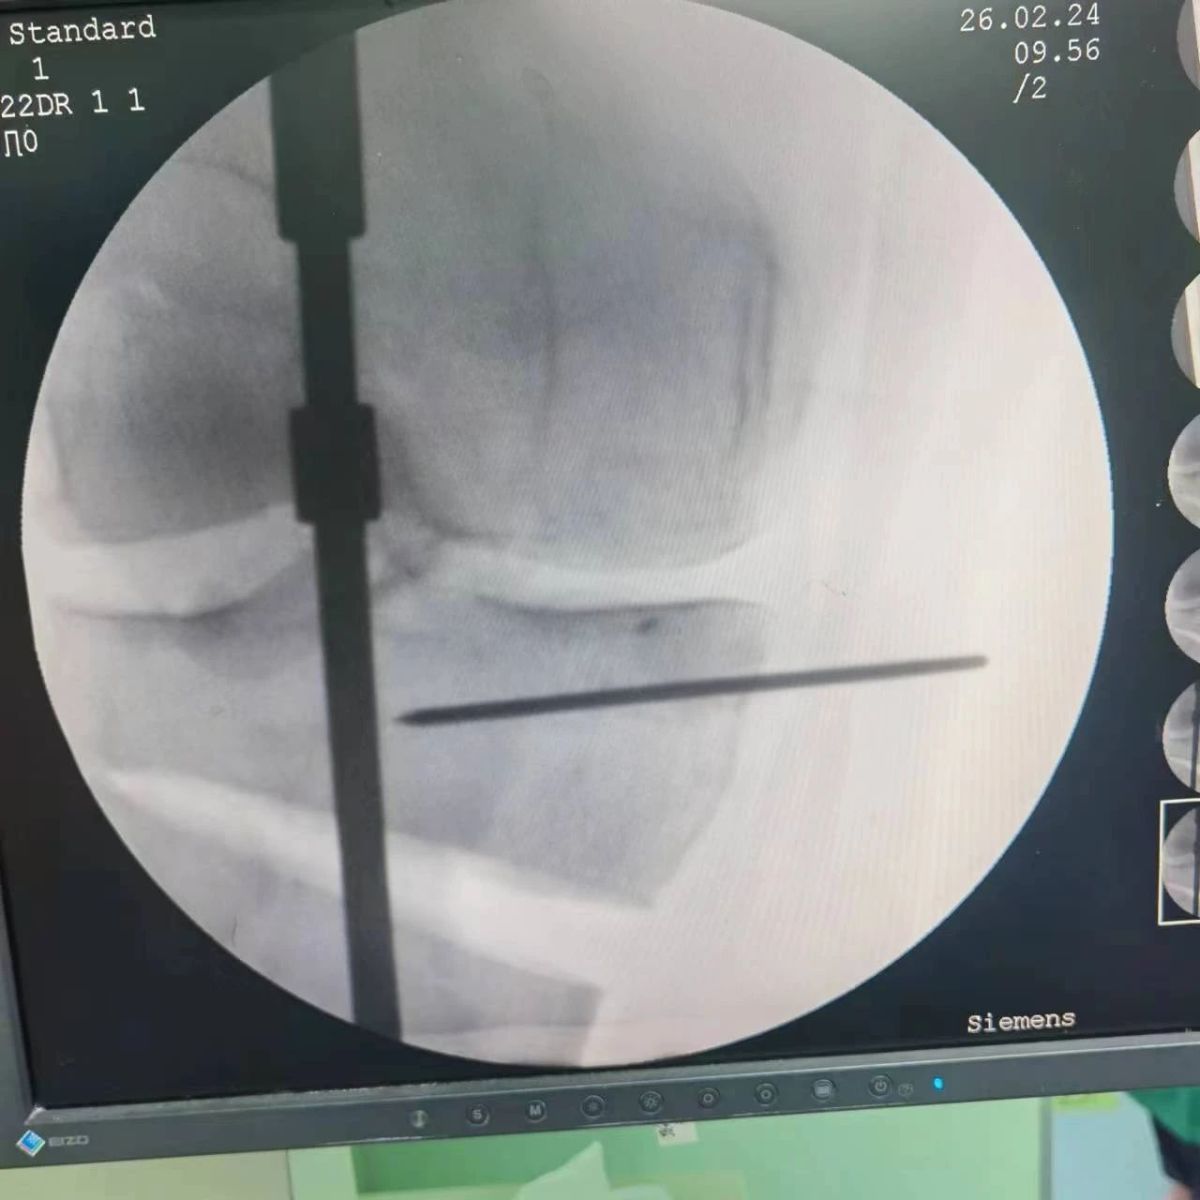

李付彬主任團(tuán)隊(duì)通過精準(zhǔn)術(shù)前規(guī)劃,設(shè)計(jì)目標(biāo)力線及調(diào)整撐開角度,轉(zhuǎn)化成需要撐開的高度,最終設(shè)計(jì)出同等高度的填充塊,術(shù)中驗(yàn)證力線調(diào)整與術(shù)前規(guī)劃完全一致!

鋼板位置、螺釘位置及長度均可通過術(shù)前規(guī)劃計(jì)算,術(shù)中通過定位操作,基本與術(shù)前規(guī)劃一致,手術(shù)快速高效完成,外側(cè)合頁保留完整。無任何并發(fā)癥出現(xiàn)。術(shù)后見鋼板位置及力線糾正近乎完美!